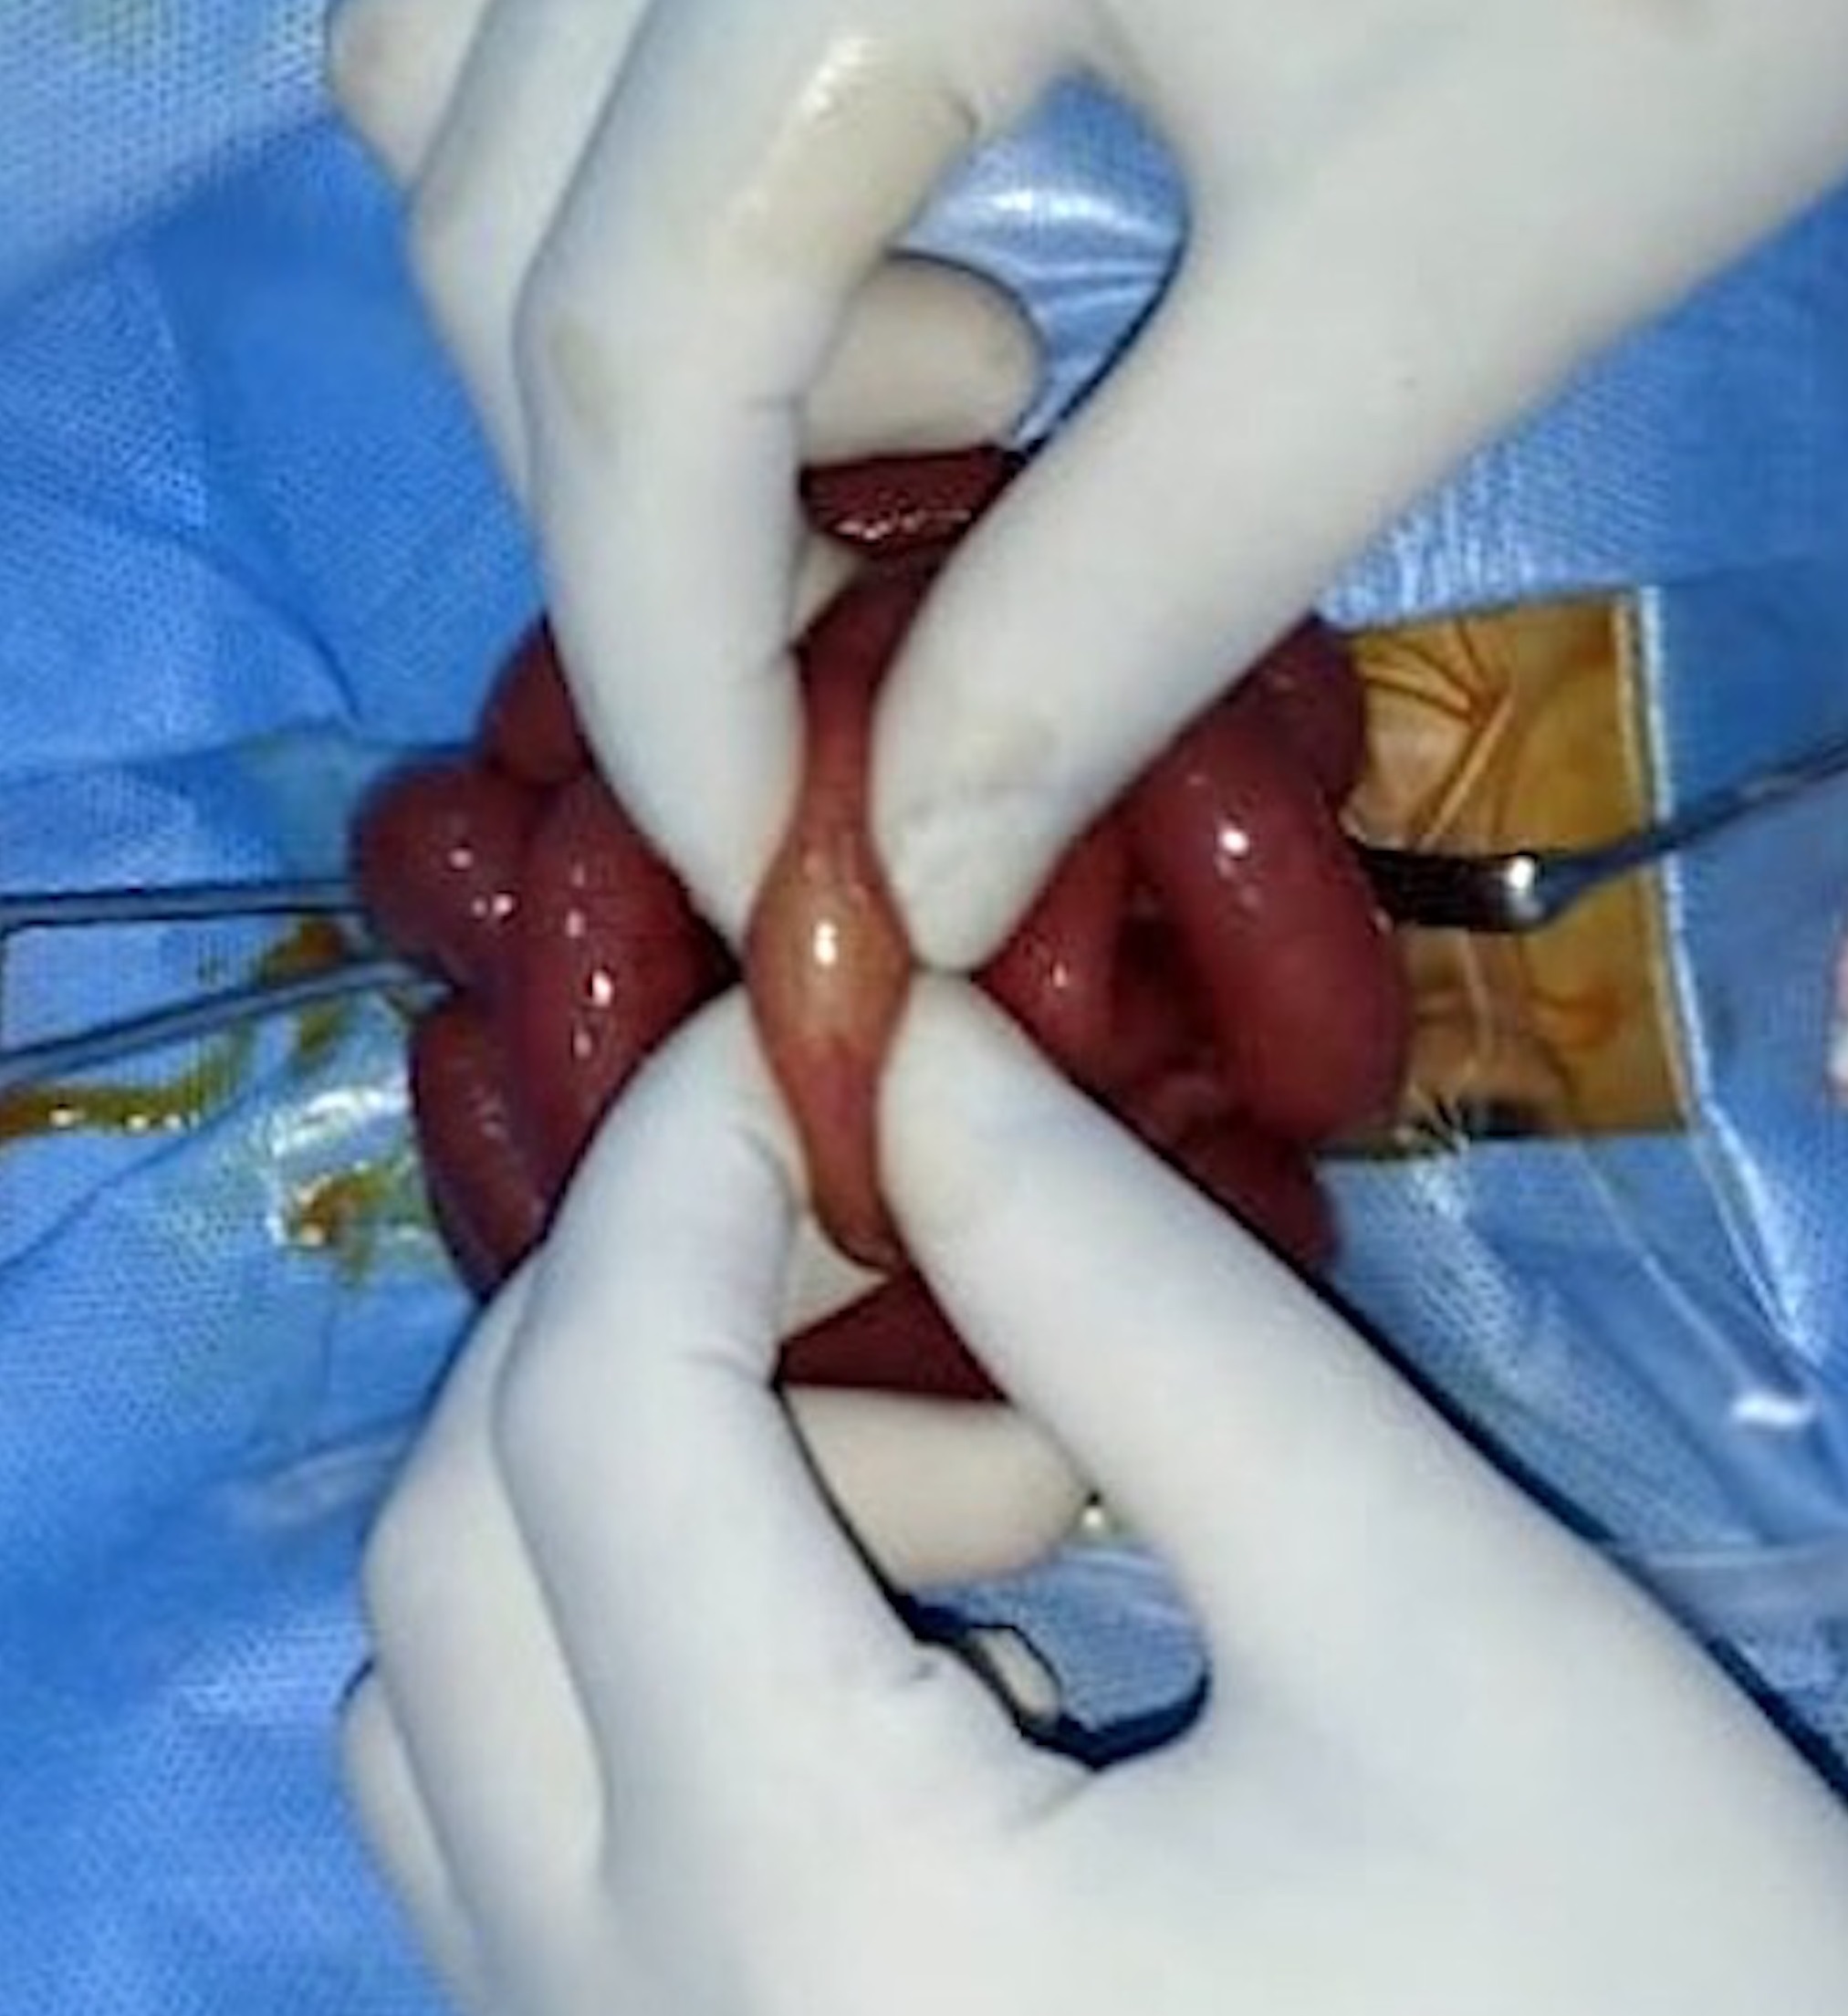

A diagnosis of intestinal obstruction was made; however, the clinical and radiological features did not point at any likely etiology. As the patient had acute intestinal obstruction, he was taken up for emergency exploratory laparotomy. The intraoperative findings showed dilated small bowel loops with an intraluminal soft, globular foreign body impacted in the distal ileum (Fig. 2). The bowel was opened longitudinally over the foreign body which was found to be a swollen raisin that had imbibed fluid and swollen up and was completely obstructing the narrow lumen of the terminal ileum (Fig. 3). The raisin was removed and the enterotomy was closed. On re-inquiry, it was found that the elder sister who was five years old, playfully put a raisin into the mouth of the newborn, which went unnoticed by the parents. Postoperative recovery was uneventful, and the patient was discharged in good clinical condition. The child was initially on 3 monthly follow up for one year. During the last follow-up, he was 2 years old, asymptomatic, and had normal developmental milestones.

Intraluminal soft globular foreign body impacted in the distal ileum.